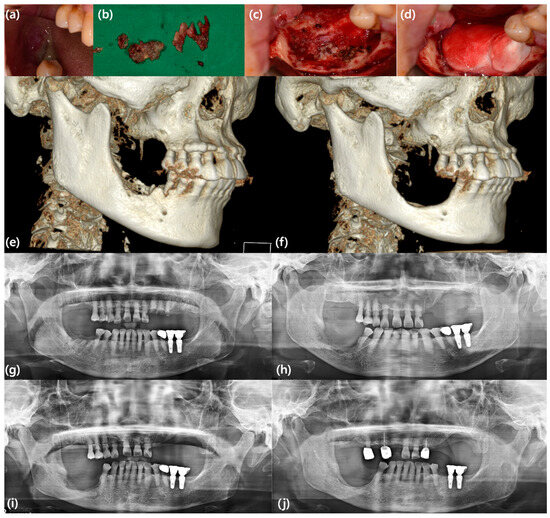

- Cicciu, M.; Herford, A.S.; Juodzbalys, G.; Stoffella, E. Recombinant human bone morphogenetic protein type 2 application for a possible treatment of bisphosphonates-related osteonecrosis of the jaw. J. Craniofacial Surg. 2012, 23, 784–788. [Google Scholar] [CrossRef] [PubMed]

- Min, S.H.; Kang, N.E.; Song, S.I.; Lee, J.K. Regenerative effect of recombinant human bone morphogenetic protein-2/absorbable collagen sponge (rhBMP-2/ACS) after sequestrectomy of medication-related osteonecrosis of the jaw (MRONJ). J. Korean Assoc. Oral Maxillofac. Surg. 2020, 46, 191–196. [Google Scholar] [CrossRef]

- Park, J.H.; Kim, J.W.; Kim, S.J. Does the Addition of Bone Morphogenetic Protein 2 to Platelet-Rich Fibrin Improve Healing After Treatment for Medication-Related Osteonecrosis of the Jaw? J. Oral Maxillofac. Surg. Off. J. Am. Assoc. Oral Maxillofac. Surg. 2017, 75, 1176–1184. [Google Scholar] [CrossRef]